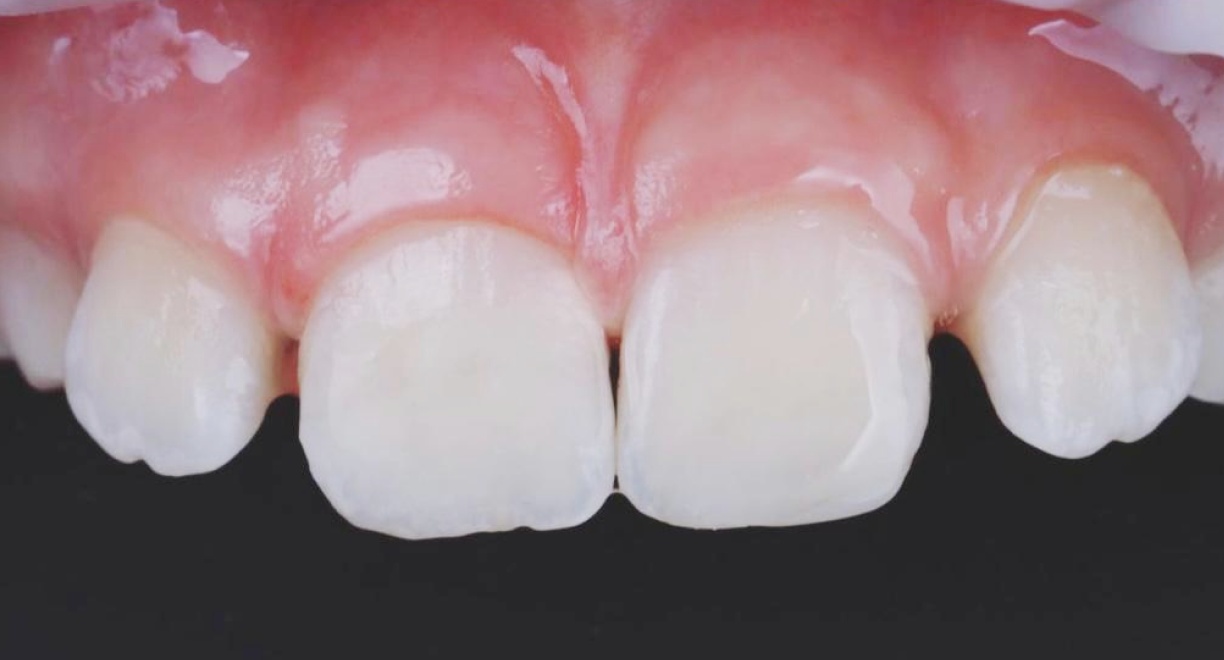

• Single-Tooth Dental Implant Placement + Dental Veneers for Full Smile Aesthetics

The patient was missing one tooth, and based on a detailed clinical evaluation, an individualized treatment plan was created. A titanium dental implant was placed into the jawbone, functioning as an artificial tooth root and providing a stable foundation for long-term restoration. After complete osseointegration, a custom-made zirconia crown was fabricated. It accurately replicates the natural tooth’s color, shape, and anatomy, restoring both chewing function and aesthetics. The neighbouring teeth are not affected during the treatment and remain intact. To ensure full smile aesthetics and a harmonious final result, dental veneers were also placed for the patient.